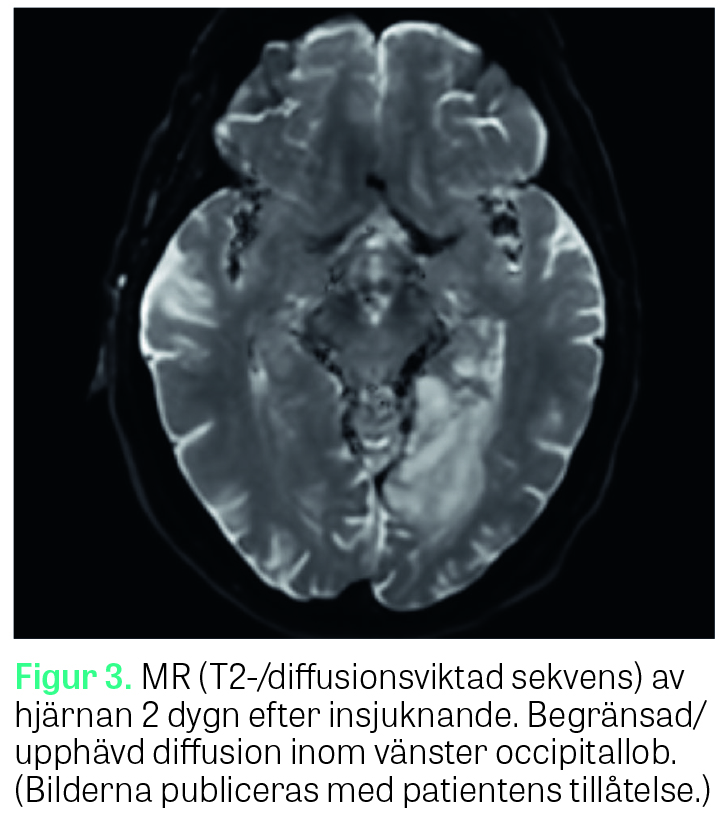

Vid klinisk undersökning på avdelningen av neurolog ett dygn senare var patienten generellt välmående. Han var helt orienterad och uppskattades till RLS 1/GCS 15. Inga motoriska eller sensoriska avvikelser uppdagades. Patienten påtalade att han märkt att han hade svårt att se på sin högra sida, vilket även konfirmerades vid Donders test då en högersidig hemianopsi upptäcktes. Patienten var dock fullt medveten om sin synfältsdefekt och märkte själv hur han kunde kompensera för den genom att vrida huvudet något extra åt höger då han till exempel tittade runt i rummet; således förelåg ingen visuell neglekt. Vid test av läsförmåga förevisas patienten korta »datorskrivna« ord och fraser på ett papper (Riksstrokes manual för NIHSS, National Institutes of Health stroke scale) som hen ska läsa högt. Vid första försöket tolkade patienten orden som siffror, och i stället för att läsa upp till exempel »Du kan«, »Jordnära« och »Jag kom hem från arbetet« läste han »fyra, sju, fem, fyra« etc. Då detta påtalades för patienten gjordes ett nytt försök, och då läste patienten i stället bokstäverna var för sig (»d«, »u«, »k«, »a« etc.). Patienten ­stakade sig ­något vid uppläsningen då han behövde tänka ­efter, men hade inga bekymmer att känna igen bokstäverna efter en stunds betänketid. Det förelåg dock en fortsatt svårighet att sammanfoga bokstäverna till ord. Vid undersökning av skrivförmåga med papper och penna kunde patienten utan bekymmer skriva till exempel »Jag befinner mig på lasarettet« och »Det är februari månad« med både bevarad stavning och handstil. Då patienten direkt efteråt ombads att läsa upp vad han själv skrivit återgick han till att stakande läsa upp bokstäverna var för sig (så kallad »letter by letter reading«) utan att kunna sammanfoga dem till ord. Undersökningen upprepades ett antal gånger för att säkerställa att det inte var patientens högersidiga synfältsdefekt som gjorde att han inte kunde läsa från vänster till höger, men samma mönster upprepades oavsett var i synfältet texten placerades. Patienten kunde på ett adekvat sätt förmedla var i synfältet han hade svårt att se och visade själv hur han kompenserade för detta. Diag­nosen alexi utan agrafi misstänktes och MR hjärna genomfördes som visade på infarktförändringar i vänster (dominant) occipitallob med engagemang av splenium corporis callosum och posteriora talamus (Figur 1–3), överensstämmande med vad man kunnat se i tidigare fallbeskrivningar av alexi utan agrafi [1, 2]. Under vårdtiden uppdagades ett förmaksflimmer på telemetri, vilket bedömdes vara genesen till patientens stroke. Patienten påbörjade behandling med antikoagulantia för att minska risken för ytterligare tromboembolism, erhöll remiss till logoped för att få hjälp med att träna upp läsförmågan och skrevs ut väsentligen välmående från lasarettet ett par dagar senare.

Syndromet alexi utan agrafi (eng: pure alexia), beskrevs av den franske neurologen Joseph Jules Dejerine redan 1892 [3] och i ett flertal fallrapporter därefter [1, 2, 4]. Alexi utan agrafi hör till gruppen »disconnection syndromes«, vilka kan uppstå av skador på nätverken mellan hemisfärerna eller mellan olika delar inom samma hemisfär [5]. De flesta beskrivna fall av alexi utan agrafi har berott på cerebrala infarkter orsakade av ocklusion i arteria cerebri posterior på den dominanta, oftast vänstra, sidan med resulterande infarkt i vänstra visuella kortex och splenium corporis callosum. Förklaringen till fenomenet är att lesionen i splenium stör kopplingen mellan den högra, icke-dominanta sidans visuella kortex och den dominanta sidans gyrus angularis, som med sitt läge i omedelbar anslutning till Wernickes språkförståelse­area har en avgörande betydelse för vår läsförmåga. Den bevarade skrivförmågan förklaras av att den dominanta gyrus angularis i sig själv lämnas intakt vid denna skadelokalisation [1, 6]. Utöver infarcering orsakad av ocklusion i arteria cerebri posterior har syndromet även kunnat ses vid glioblastom [7] och multipel skleros [8].